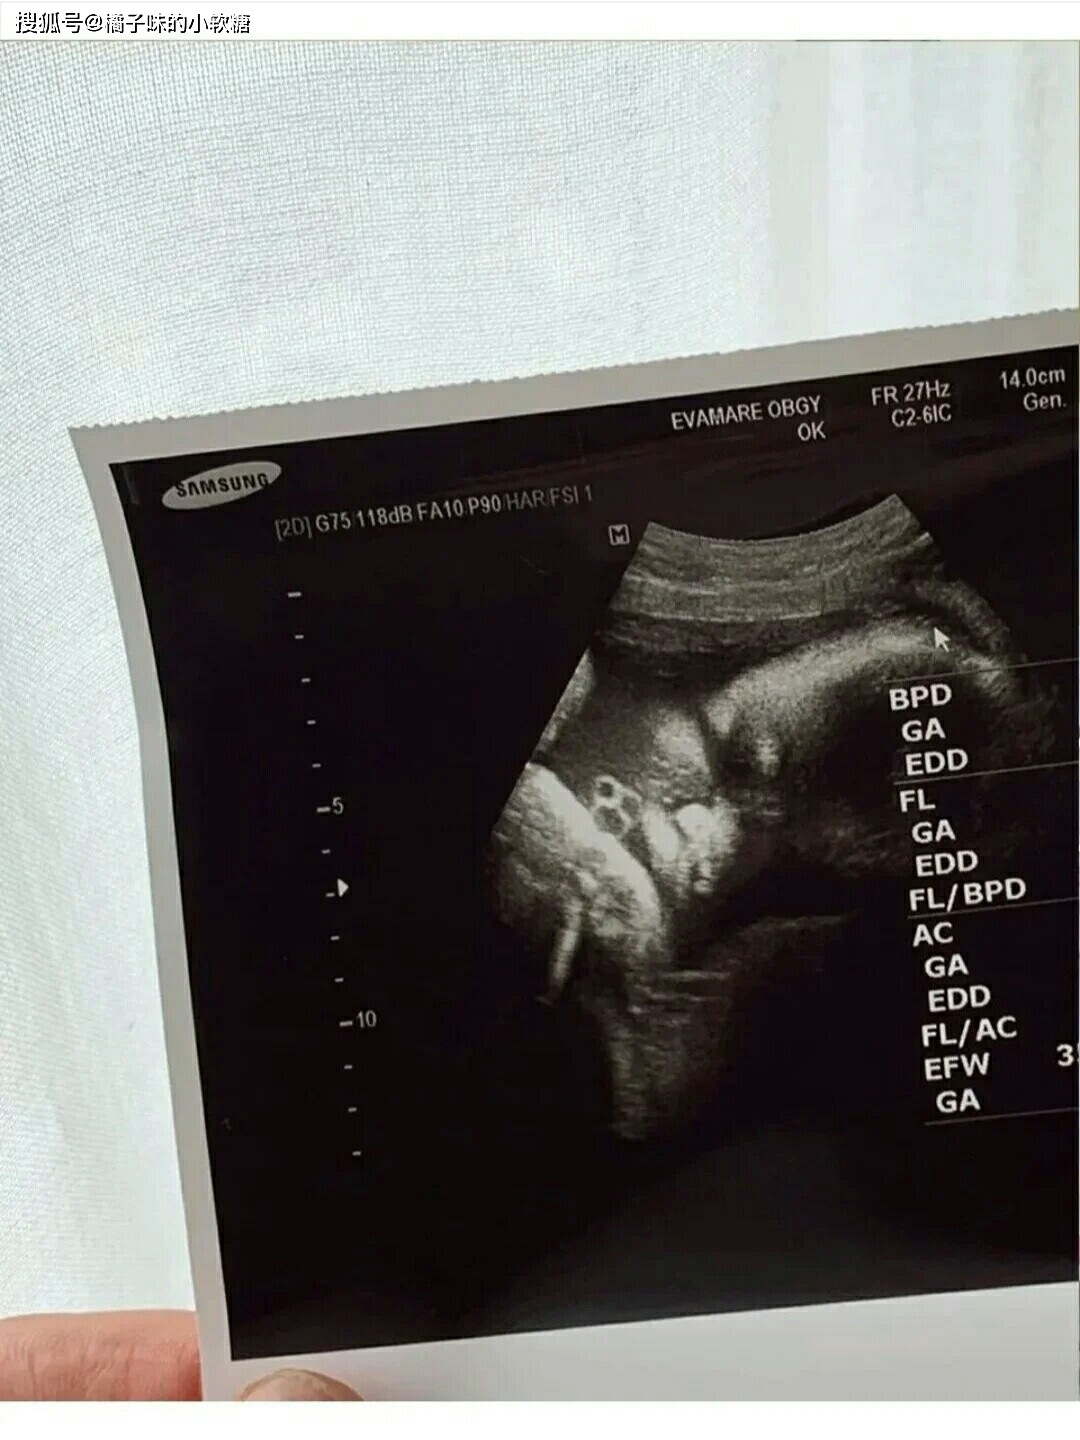

孕男宝生殖彩超图,男宝彩超图片男女

男宝彩超图片男女

男宝b超图典型的

最明显的男宝b超图

男宝彩超图片

男宝彩超小鸡图片

男宝b超图片

最明显的男宝宝彩超图